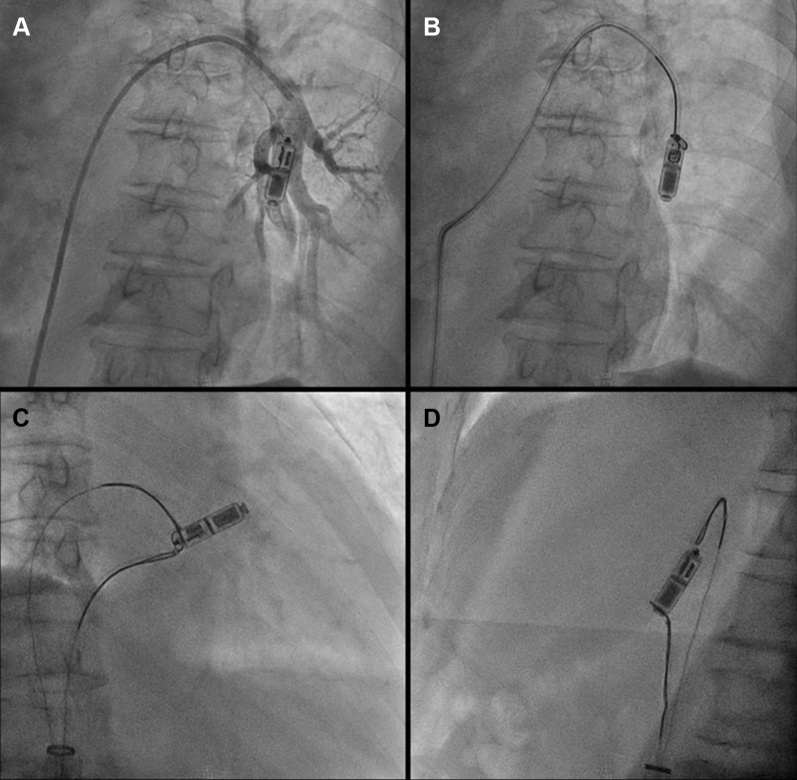

Figure 1.

A: Left anterior oblique view and B: right anterior oblique (RAO) view showing apical position of the final implant attempt. C: Final deployment position in RAO view. Note the naturally upward curve of the delivery catheter, making it unfavorably aligned with the Micra transcatheter pacing system. D: RAO view showing acute angle between the deployed device and the recapture cone when tether is pulled.

The first 2 deployments at mid and low interventricular septum resulted in high pacing thresholds steadily greater than 3.0 V at 0.24 ms, although R-wave amplitudes were more than 5 mV and impedances were within range. Device recaptures were performed uneventfully. The third implant at the right ventricle (RV) apex yielded similar results. Device retrieval from the apex, however, was more difficult owing to the unfavorable angle between the recapture cone and the Micra (Figure 1). After prolonged manipulation, the Micra was dislodged from myocardial anchorage. While the operator attempted to realign the dislodged leadless pacemaker by gently pulling the tether, there was a sudden give-way sensation and the tether was found broken. As a result, the leadless pacemaker embolized to the inferior branch of the left pulmonary artery.

The device and delivery catheter were examined after retrieval. The tether was found to be broken approximately mid length, with evidence of damage likely owing to mechanical abrasion during recapture attempts (Figure 3). We postulate that the acute angle between the recapture cone and the apically implanted Micra constituted a hinge point at the edge of the recapture cone (Figure 1D). The tether got abraded over the edge of the recapture cone during multiple recapture attempts, which caused its gradual weakening. After dislodgment from myocardial anchorage, the Micra became completely misaligned with the cone and the tether broke with additional tension.

Device repositioning after deployment is commonly performed to achieve adequate fixation or electrical parameters.4 To perform recapture, it is recommended to apply tension to the tether while advancing the delivery system until the recapture cone is in contact with the device.7 The operator should then make sure that the recapture cone and device are coaxial before locking the tether and retracting the device. The natural upward curvature of the delivery catheter may make this maneuver difficult in small hearts (Figure 1C). With an apically deployed device, an acute angle may form between the device and recapture cone when one pulls the tether. Repeated recapture attempt in this situation could rub the tether against the edge of the recapture cone and weaken it significantly.